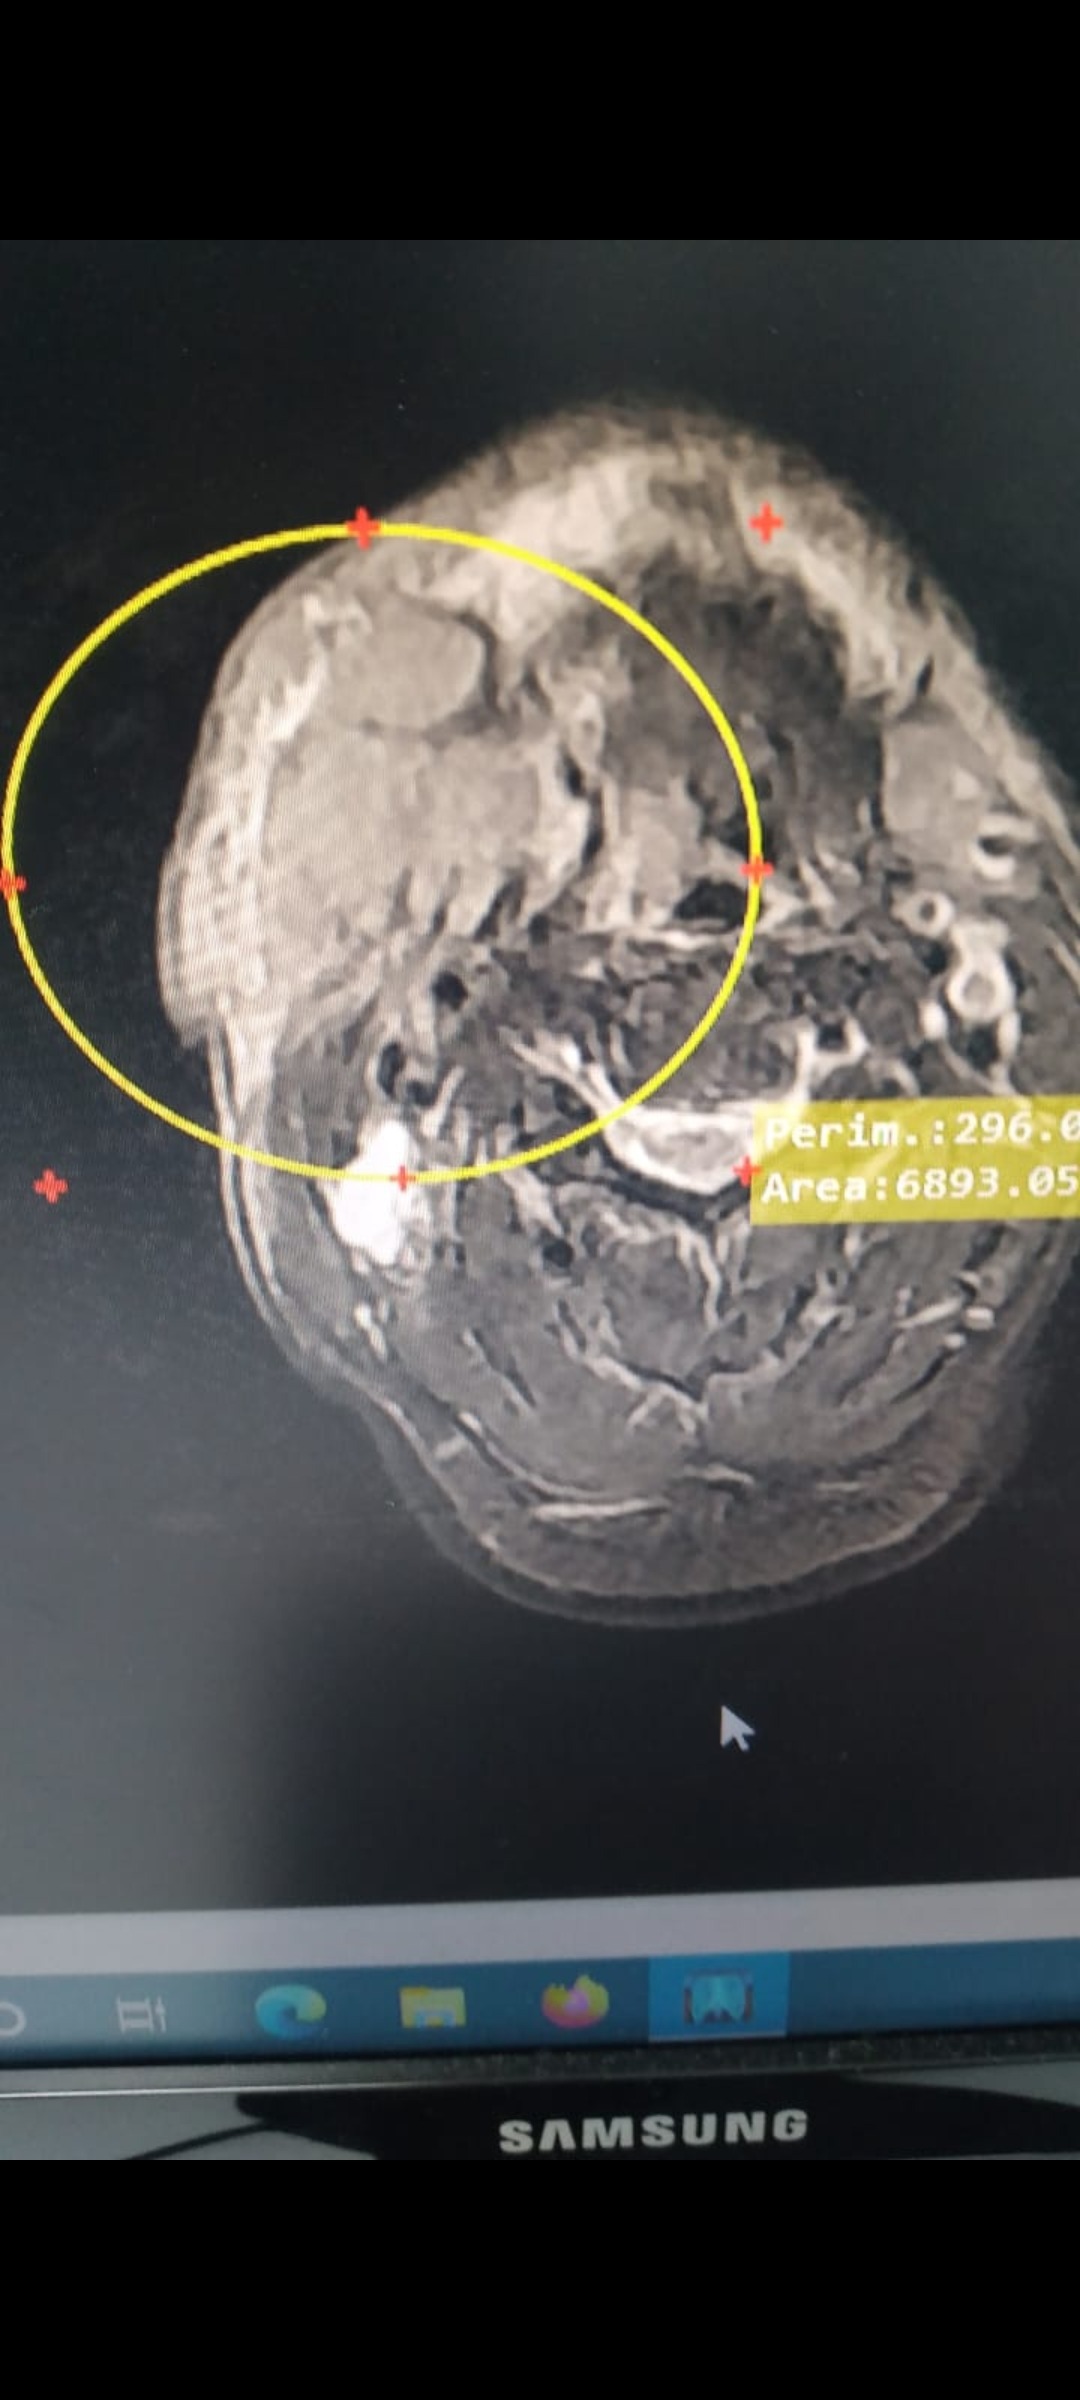

My sister-in-law's husband is facing a devastating battle with cancer. The malignancy developed on his face, beneath his tongue, making it nearly impossible for him to eat and causing him constant pain. His condition has left him frail, thin, and malnourished, but despite everything, he holds onto a strong will to live.